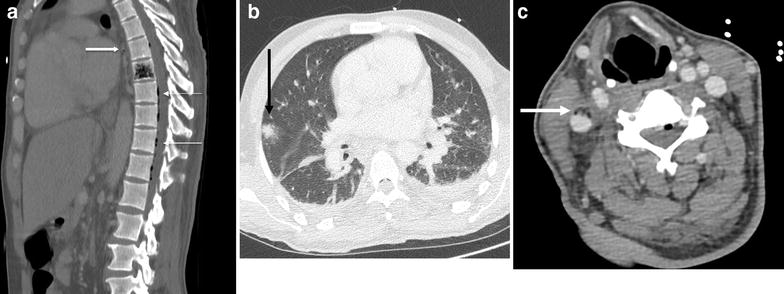

A 48-year-old man presented to the emergency department with back pain, fever and confusion, 1 week after a sore throat ascribed to pharyngitis. The patient was admitted to the ICU for septic shock and a computed tomography (CT) was performed. CT depicted an air infiltration of the D8 vertebral body, diffuse epidural pneumatosis, pneumomediastinum and pulmonary nodules (Fig. 1a, b). Because of the initial pharyngitis, we suspected the possibility of Lemierre’s syndrome, a complication of oropharyngeal infection defined by septic thrombophlebitis of the internal jugular vein (Fig. 1c) and distal emboli that most commonly involved the lungs [1]. Most cases are caused by Fusobacterium necrophorum, which was identified in the patient’s blood cultures and cerebrospinal fluid. The symptomatology was finally attributed to Lemierre’s syndrome with an unusual case of vertebral dissemination. The patient received intravenous amoxicillin for 4 weeks and metronidazole for 8 weeks. Considering that some strains have been reported to produce β-lactamases, metronidazole is commonly prescribed for its bactericidal activity and excellent penetration into most tissues. The combination of β-lactam and metronidazole achieves coverage of co-infecting oral streptococci. The patient fully recovered and was discharged from the hospital on day 35.

Fig. 1

a Sagittal view of the chest CT scan showing vertebral pneumatosis (D8 level), extensive epidural pneumatosis (fine arrows) and pneumomediastinum close to the D8 vertebra (thick arrow). b CT scan showing a pulmonary nodule (thick arrow). c CT scan showing right internal jugular vein thrombosis (thick arrow)